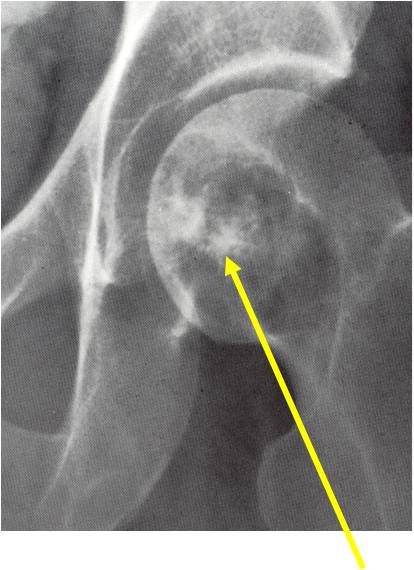

Sites:

- Epiphyses of long bones

- Most commonly proximal femur, proximal humerus, distal femur, proximal tibia

Radiographic Presentation

- Usually osteolytic, expansile lesion

- May be focally calcified

- Often a sharp interface between tumor and surrounding bone

- Sclerotic rim is uncommon

- Overlying cortex is usually thin, but intact